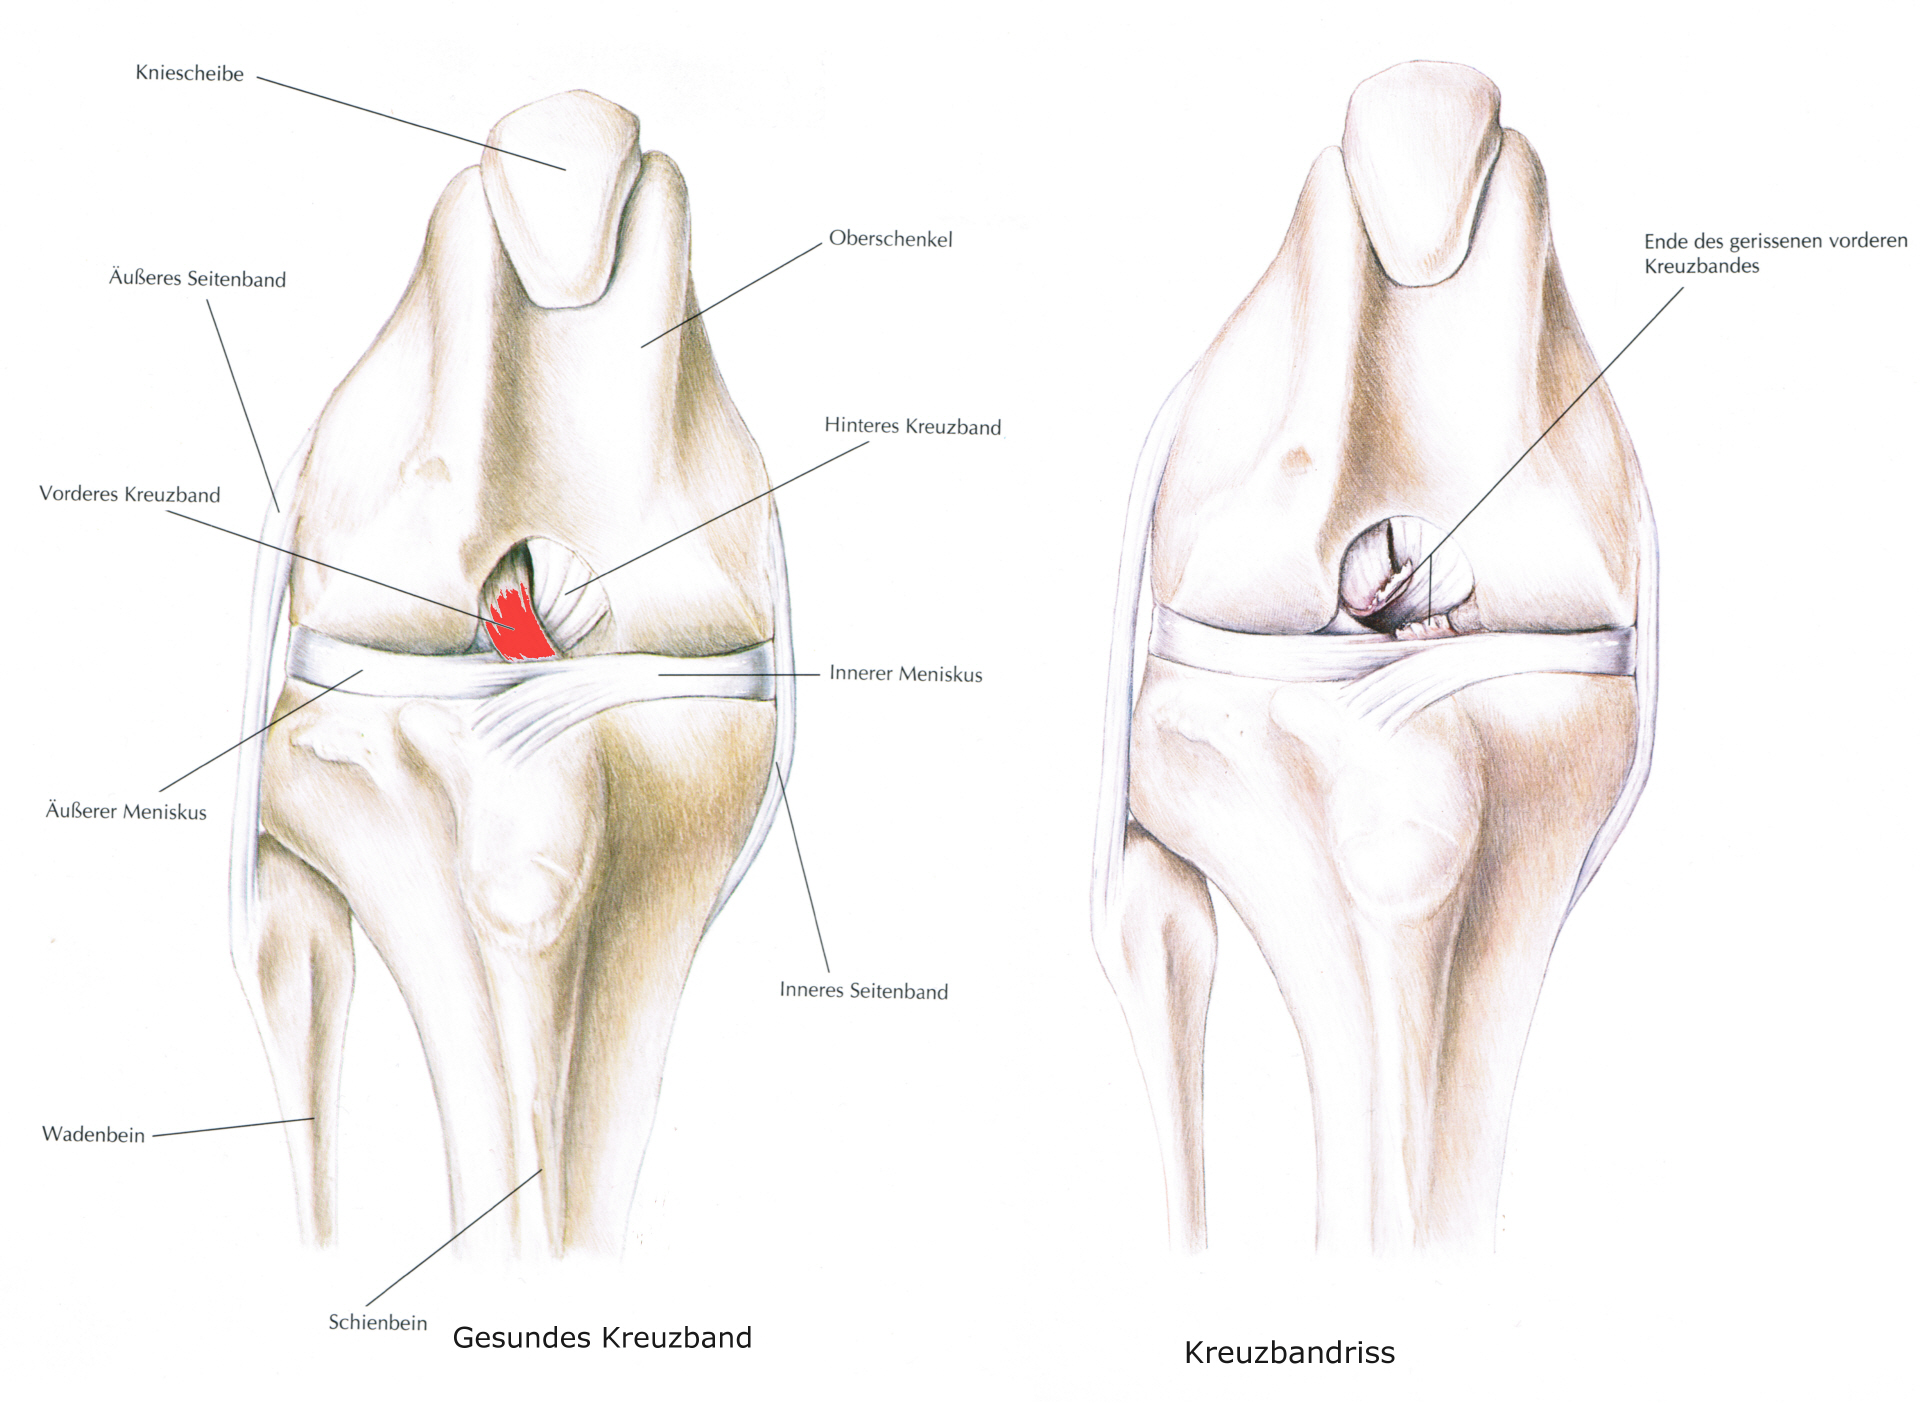

Der Kreuzbandriß beim Hund ist im Gegensatz zum Menschen in 90 % der Fälle nicht durch einen Unfall verursacht sondern eine Folge von degenerativen Prozessen im Gelenk wie z. B. einer Gelenksarthrose. Begünstigt wird diese Erkrankung z. B. durch Übergewicht. Deshalb geht der betroffene Hund meistens ohne deutlich erkennbare Ursache plötzlich lahm. Beim Neufundländer und Boxer ist eine genetische Anlage bewiesen. Generell gilt aber, dass vor allem ältere kastrierte Hündinnen (> 6-7 J) mit Übergewicht betroffen sind. Die betroffenen Tiere zeigen eine zumeist deutliche Lahmheit am betroffenen Hinterbein. Die Diagnose wird beim Tierarzt durch eine Ganganalyse, den Sitztest, eine umfassende klinische Untersuchung (z. B. Schubladenphänomen, Tibiakompressionstest) und Röntgendiagnostik gestellt. Eine Röntgenuntersuchung in mind. 2 Ebenen ist zwingend erforderlich um weitere Erkrankungen (z.B. eine Arthrose oder eine OCD) festzustellen.